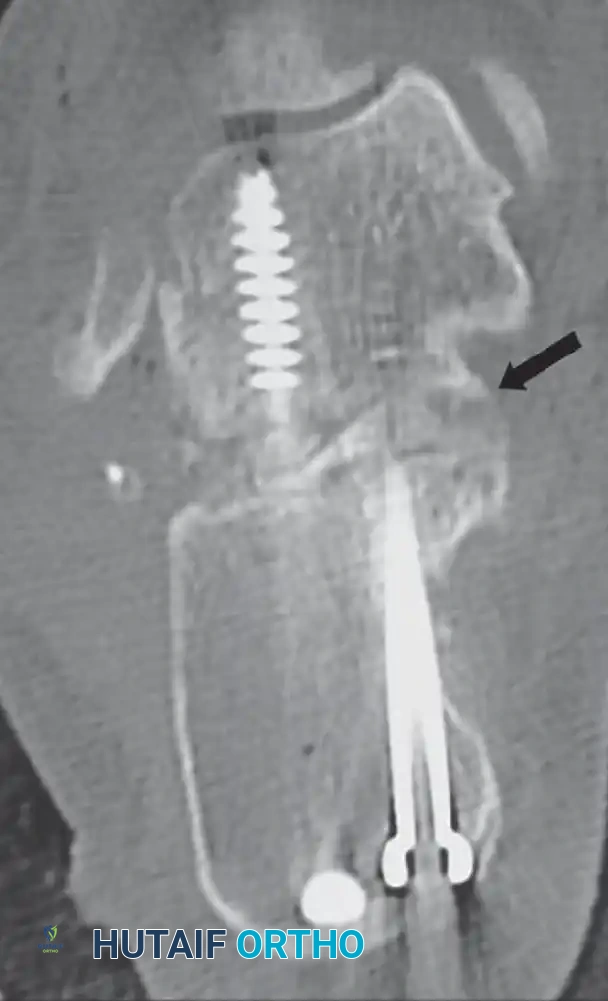

A fine-cut computed tomography (CT) scan with sagittal and coronal reconstructions is the definitive imaging modality. Coronal cuts precisely quantify the lateral wall blowout and the status of the posterior facet of the subtalar joint. Sagittal cuts evaluate the calcaneocuboid joint, which may also be arthritic and require concurrent management.

- Verify the correction of the varus deformity, the restoration of calcaneal height, and the decompression of the subfibular space using intraoperative fluoroscopy (AP, lateral, and Harris axial views).

- Definitively fix the subtalar arthrodesis using two or three large-diameter (6.5 mm or 7.3 mm) cannulated, partially threaded cancellous screws. Insert the screws from the calcaneal tuberosity, directing them anteriorly and superiorly into the body and neck of the talus to achieve maximal compression across the arthrodesis site.